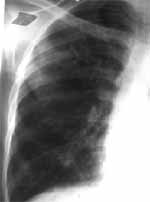

Un mes más tarde por progresión de los síntomas consulta nuevamente. Se toma radiografía de tórax que evidencia opacidad del lóbulo superior izquierdo (Figura 1). Ecografía torácica sugiere empiema.

Figura 1A. Figura 1B. Opacidad parenquimatosa de bordes

bien definidos en el lóbulo superior izquierdo.